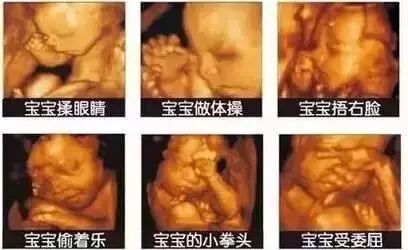

5D四维彩超与其他彩超的呈像区别

5D四维彩超在二维三维四维的基础上,更直观更清晰地呈现胎儿在宫内的动态图像,多方位多角度地观察宝宝的生长发育情况,还能够对孕妇潜藏的各类疾病进行精确检测。

5D四维,能自动为胎儿进行宫内拍“写真”和动态录像,为准妈妈增添了不少情趣。她们不再是仅仅感觉宝宝运动,而且可以亲眼目睹肚子里宝宝的乖巧容貌和可爱动作。